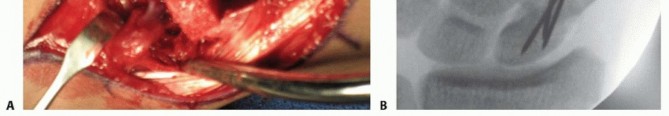

Incision, Exposure, and Pedicle Dissection

The surgical approach requires precision and a profound respect for the delicate dorsal soft tissues. With the tourniquet inflated (without prior Esmarch exsanguination), a gently curving, lazy-S or curvilinear incision is designed over the dorsoradial aspect of the wrist. The incision is centered precisely over the anatomical interval between the first and second dorsal extensor compartments, extending approximately 4 to 5 centimeters. The proximal extent reaches the distal radial metaphysis, while the distal extent curves gently toward the anatomic snuffbox and the scaphoid.

The skin and subcutaneous tissues are sharply incised. Extreme care must be taken during the subcutaneous dissection to identify, mobilize, and protect the sensory branches of the superficial radial nerve, which frequently cross the operative field. Retraction of these nerve branches should be gentle, utilizing vessel loops rather than rigid retractors to prevent neurapraxia. As the subcutaneous fat is cleared, the transverse fibers of the extensor retinaculum come into view. At this stage, the surgeon must utilize surgical loupes (minimum 2.5x to 3.5x magnification) to identify the 1,2 IC SRA. The vessel, accompanied by its paired venae comitantes, will be visible as a distinct longitudinal neurovascular bundle coursing distally on the superficial surface of the retinaculum, exactly between the first and second compartments.

To mobilize the pedicle safely, the retinaculum must be unroofed. The critical technical pearl here is to avoid cutting directly over the artery. Instead, the retinaculum is incised longitudinally over the radial aspect of the first dorsal compartment (exposing the APL and EPB) and over the ulnar aspect of the second dorsal compartment (exposing the ECRL and ECRB). By elevating these retinacular flaps toward the midline interval, the surgeon creates a continuous, robust strip of retinaculum that contains the 1,2 IC SRA safely within its substance. This perivascular cuff of tissue protects the delicate microvasculature from sheer stress and preserves the vital venous drainage network.